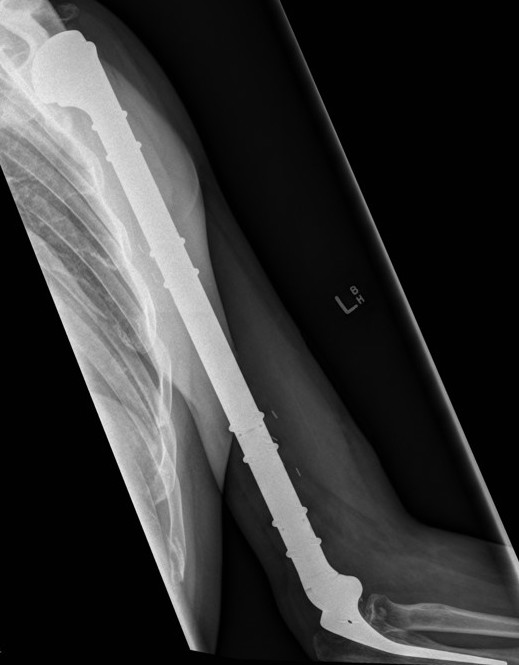

- proximal humerus 10%

Osteosarcoma of the humerus Osteosarcoma of the fibula

Post distal femoral osteosarcoma resection